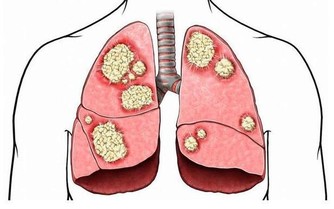

皮膚瘙癢、發黃:肝膽疾病

如果出現全身性的瘙癢,同時皮膚、眼睛、尿液等異常發黃,有可能是患上肝膽疾病的表現。

皮膚瘙癢、有異味:腎病

腎臟功能出現問題,無法排出的廢棄物質,導致皮膚受到刺激,不僅會瘙癢難耐、乾燥無光,還可能出現尿腥等異味。

皮膚瘙癢、飯量變大、體重變輕:糖尿病

皮膚瘙癢同時伴有多飲、多尿、多食和消瘦的症狀,則可能是糖尿病導致的瘙癢。

數據顯示,約有10%的早期糖尿病患者會出現全身性或局部性的皮膚瘙癢,尤其在腋窩及腹股溝的部位最嚴重。